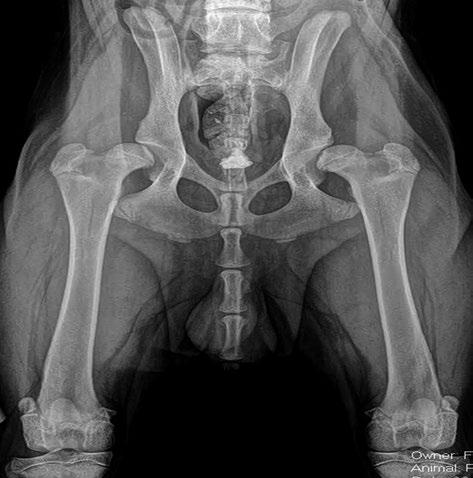

Issuu converts static files into: digital portfolios, online yearbooks, online catalogs, digital photo albums and more. Sign up and create your flipbook.